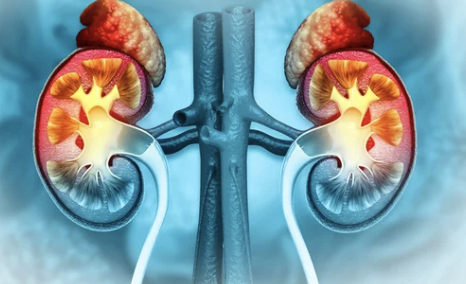

📌 1. 부신암이란? – 부신의 역할부터 알아보자!

✔ 부신(Adrenal Gland)은 신장 위에 위치한 작은 내분비기관으로

✔ 호르몬 분비를 담당하며, 스트레스 반응, 혈압 조절, 신진대사 등에 중요한 역할을 합니다.